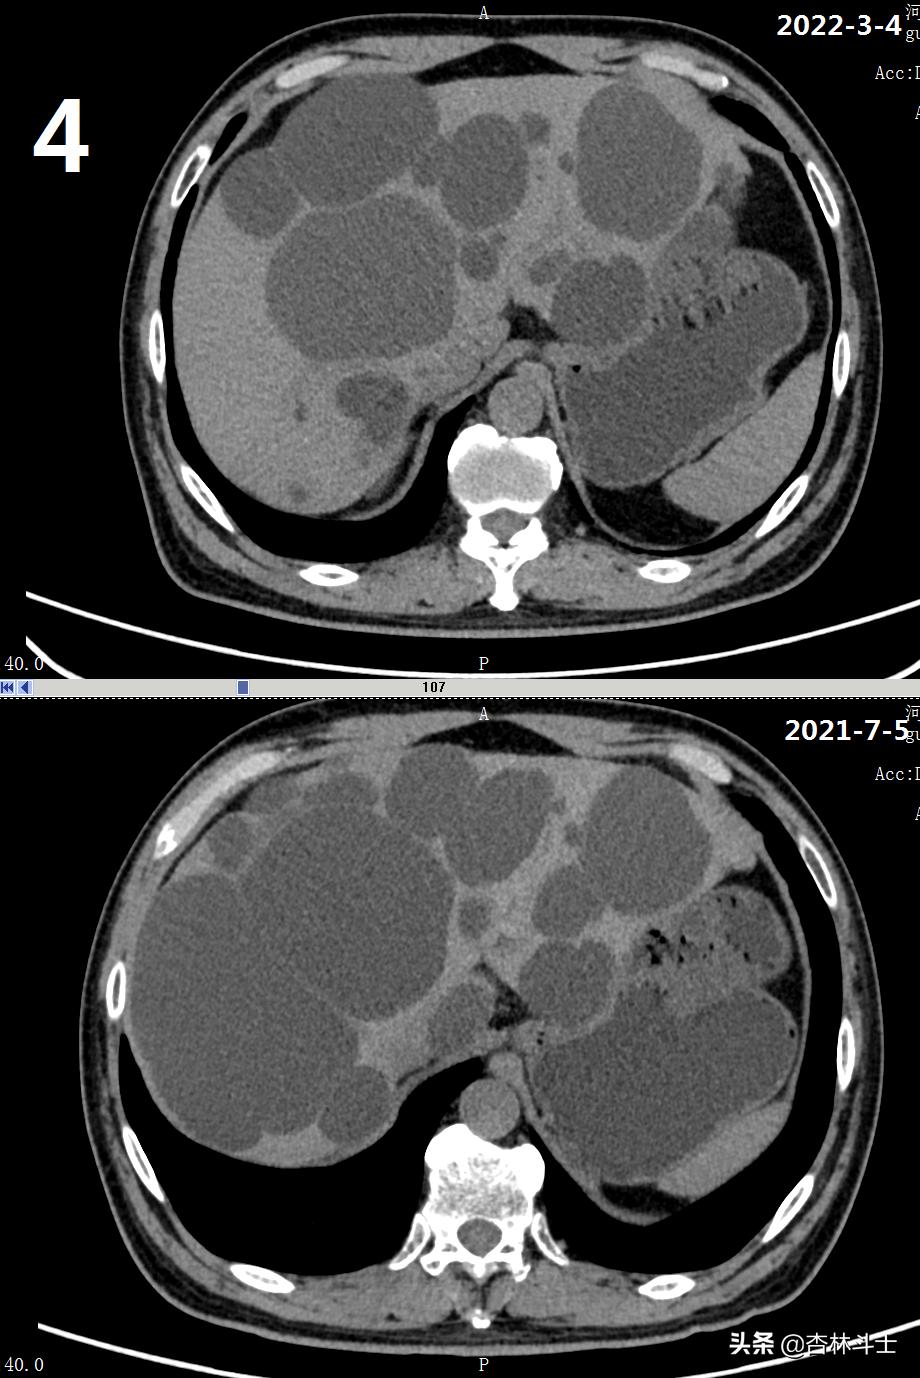

64岁退休银行职员,腹胀5年,加重2月,第二次入住我院消化内科。下图1-6为本次复查上腹部CT与2021-7-5肝囊肿经皮肝穿刺抽吸无水酒精硬化术前的对比图。

可明显看出,肝内囊肿较前减少,肝实质所占体积明显增加。